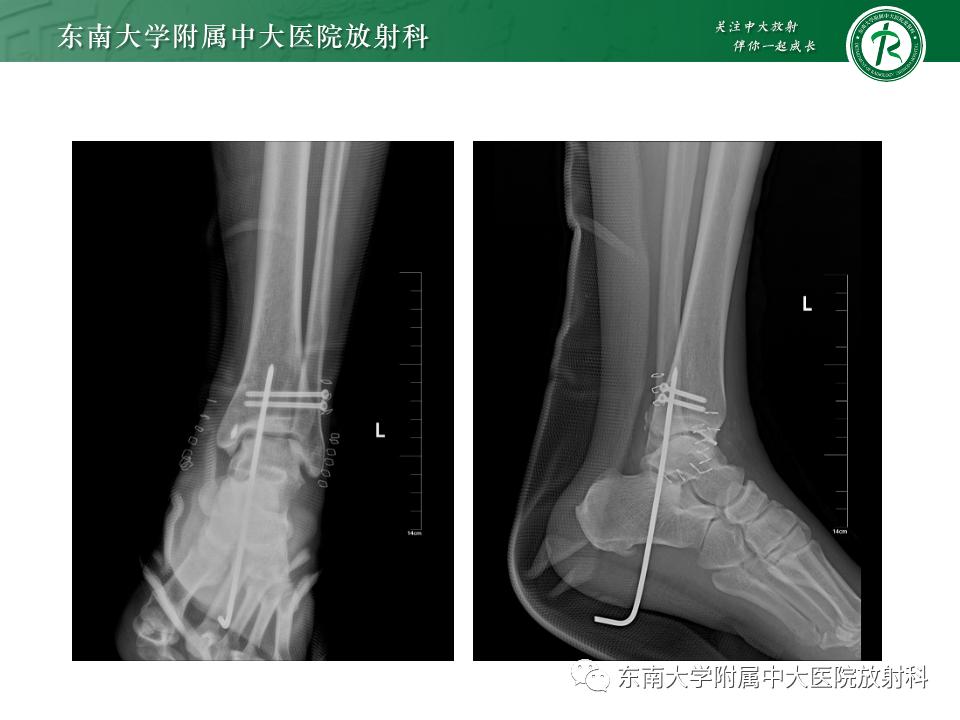

影像学表现

左腓骨下段骨折伴下胫腓联合分离,好文分享深度揭秘